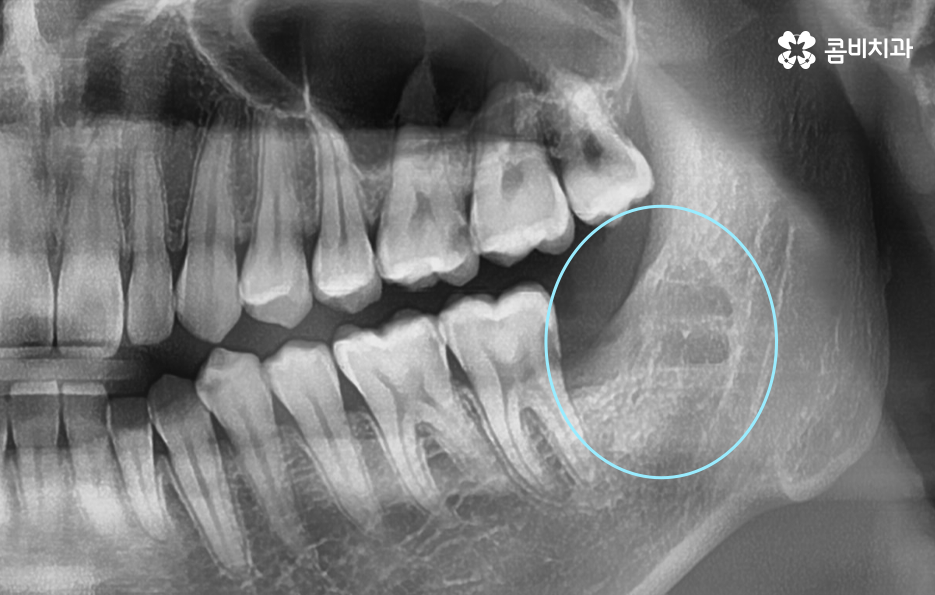

이제 부분매복 사랑니 발치 방법에 대해 좀더 알아보면 사랑니 발치는 단순히 치아를 뽑는 것이 아니라, 잇몸 절개, 치아 분할, 신경 보호 등 여러 과정을 정교하게 고려해야 하기 때문에 첫 번째 단계는 정확한 진단 과정이 우선되어야 할 수 있어요

부분매복 사랑니는 겉으로 보이는 부분만으로는 실제 뿌리 모양이나 뿌리의 깊이를 알 수 없으며 X-ray만으로는 앞 어금니와 얼마나 근접해 있는지, 신경과의 거리, 뼈의 형태를 충분히 판단하기 어렵기 때문에 CT 촬영이 권장되는 경우가 많으며 CT는 3D 분석이 가능하기 때문에 사랑니 발치 시 사고 위험을 줄일 수 있고 절개 방향 등을 정확히 계획하는 데 큰 도움이 되고 있었어요